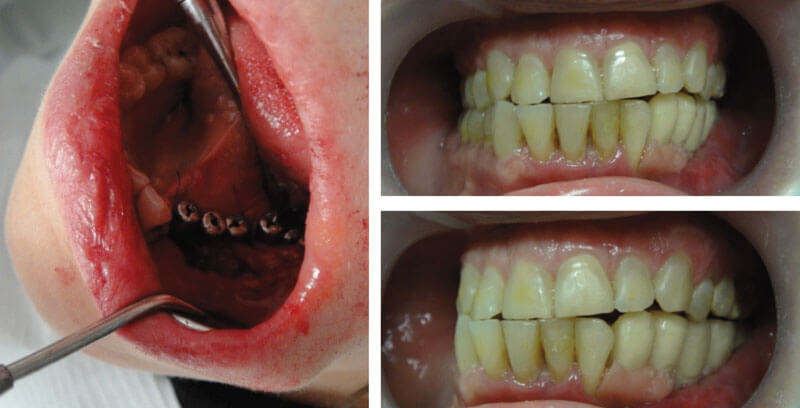

Реабилитация пациента с Постонкологическим деффеком носа, с атрофией мягких тканей после лучевого лечения

На этапе лечения после реконструкции наружного отдела носа тканевым трансплантатом на сосудистой ножке

Постонкологический деффект носа, с атрофией мягких тканей после лучевого лечения

• восстановление челюсти

• пересадка челюсти